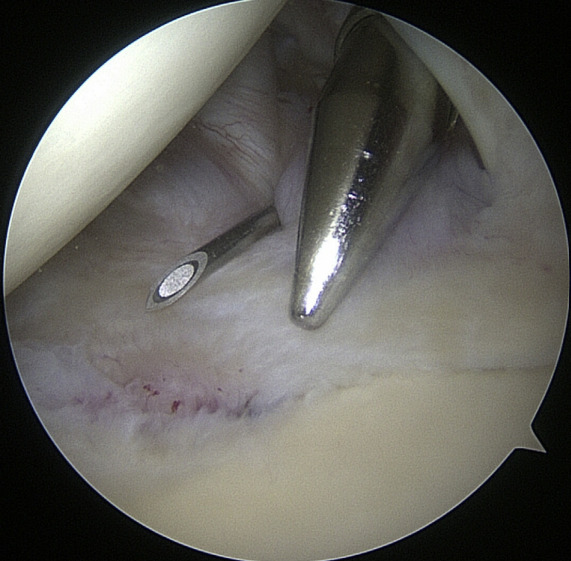

Arthroscopic shoulder surgeries are among the most common minimally invasive procedures (MIS) used to restore shoulder function. Shoulder arthroscopy and arthroscopic rotator cuff repair rates, broken down by geographic location, ranged from 64.96 to 623.6 per 100,000 persons in more recent research.23 The most frequent orthopedic operation for partial meniscectomy is knee arthroscopy, followed by shoulder arthroscopy. Shoulder arthroscopy is a common method for treating pathologic shoulder conditions including adhesive capelusitis, subacromial impingement, illnesses affecting the proximal biceps, rotator cuff tears, labral tears, loose bodies, and degenerative arthritis. Management of shoulder instability and rotator cuff pathology are the two most prevalent reasons for arthroscopic shoulder surgery. There are many advantages of arthroscopy over open surgery. Some of them include a better ability to see intra-articular disease, less complications, shorter recovery times, and less time away from work.6

Joint surgery needed large incisions and arthrotomies to expose and treat joint pathology before arthroscopy and its specialized equipment were widely used in clinical settings. Comparing arthroscopy to such lengthy open arthrotomies, there are a number of benefits. In contrast to MIS arthroscopic treatments, the longer joint exposure results in increased discomfort and recovery time, as well as an increased risk of consequences like infection and arthrofibrosis. Compared to traditional procedures, MIS operations typically cause less discomfort and swelling after surgery. Patients who have arthroscopic treatment so typically recover more quickly, start their rehabilitation earlier, and are able to resume regular activities and employment sooner.22,23

Preliminary surgical planning will establish the exact location of the anterior portal. Arthroscopy techniques for rotator cuff or biceps tenodesis usually include positioning the anterior portal centrally in the rotator interval, near the subscapularis tendon. It is common practice to use two anterior portals while performing arthroscopy on labral disease. The anteroinferior portal, which is often the working portal, is typically located around the subscapularis tendon. An extra portal called the anterosuperior portal may be used for suture inspection or shuttletling without damaging the supraspinatus tendon. Its location is directly above the biceps tendon or just slightly ahead of it. A common technique for creating these portals is the “outside-in” approach, which involves inserting a spinal needle under direct arthroscopy view to determine the correct portal location.6

Setup

The coracoid, acromioclavicular joint, clavicle, and acromion are all marked on the skin. If subacromial work is going to be performed, the subacromial bursa may be infiltrated with up to 30 cm3 of a mixture of 0.25% bupivacaine and epinephrine. A standard posterior portal is the typical site of access to the subacromial area and glenohumeral joint. The typical placement of this opening is 2 centimeters medial and 2 centimeters distal to the posterolateral border of the acromion. Palpating the soft tissues of the posterior glenohumeral joint is a common way to confirm the proper position. An anterior portal develops after the joint has been inserted. Figure 4 shows that the surgeon has the option of employing a spinal needle to perform it from the outside in or an inside out approach, depending on his or her choice. The anterosuperior portal is located just off the outside edge of the acromion. You may find the anteroinferior portal directly on the side of the coracoid. One centimeter below the anteroinferior portal is the 5 o’clock portal, which is defined as passing through the subscapularis tendon. Scientists say this entry point is the most common and least invasive as it mimics neurovascular systems. Any anterior portal may be used to conduct basic shoulder arthroscopy. Figure 5 shows the setup of both anterior portals for biceps tenodesis, subscapularis repairs, and labral repairs. For posterior labral repairs, spinal needle localization allows for the creation of an auxiliary posterolateral portal situated immediately distal to the posterolateral limit of the acromion. Anterior positioning of the Wilmington portal, one centimeter laterally to the posterolateral margin of the acromion, is recommended for superior labral repairs. The posterolateral and Wilmington portals are types of trans-rotator cuff tendon access points. Cannulas with the smallest diameters necessary should be used.25